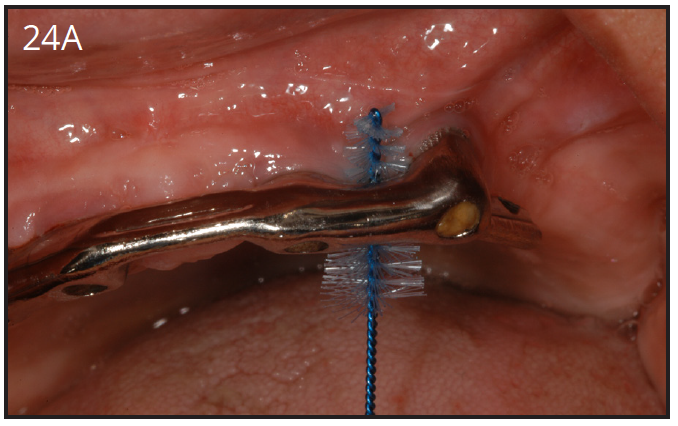

Home care for dental implant restorations is the same as for natural teeth. Daily brushing and flossing are mandatory to remove plaque build-up, which can cause peri-implant mucositis (gingivitis) and worse, peri-implantitis. Patients rely on the dental team to give them instructions on how to clean their implants. It is important to be comfortable to show the patients how to use any new oral hygiene device that the doctor may recommend. (Figure 24A)

Figure 24A – Proxybrush is a great tool to clean under the overdenture bars

Figure 24A